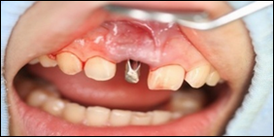

仮歯をつけるための土台です。

手術当日の仮歯です。

他院では歯を抜いて3か月程して、骨が回復した後にインプラントを入れる為、治療期間が半年かかると言われました。しかし当院では抜歯即時埋入という、歯を抜いて当日にインプラントを入れる治療法を行ったため3か月で治療を終える事が出来ました。

また抜歯即時埋入と同時に抜歯即時加重という、インプラントを埋入した当日から物を噛めるような歯を入れる治療法を併用したため、治療期間中、前歯部でも審美性を失わずに治療をすることができました。